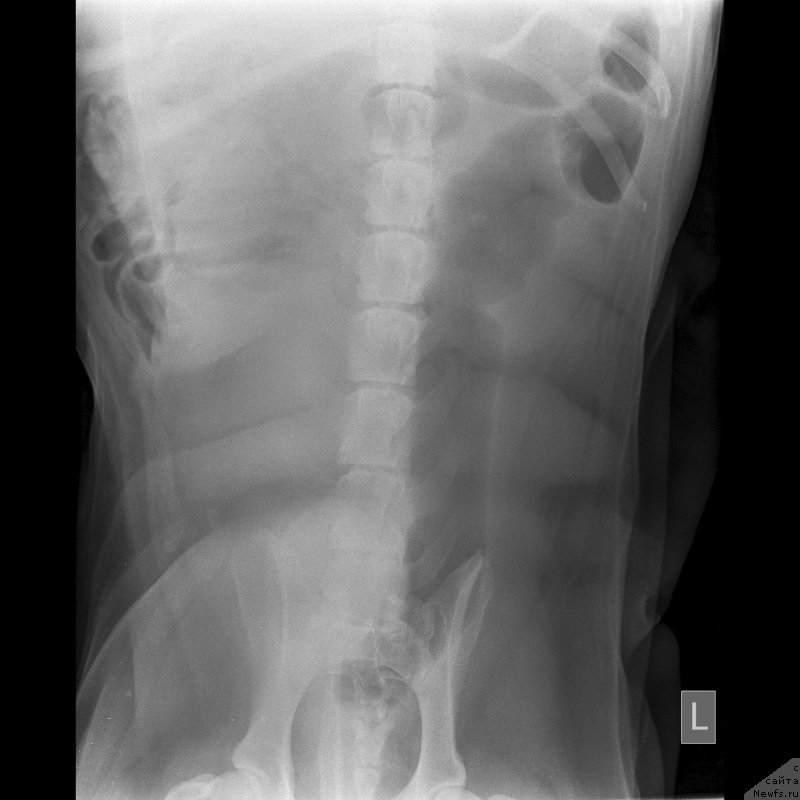

Второй ветеринар сделал ренген, где ничего не видно кроме начинающегося артроза.Опасения что слопал кость-отмели.

Сделали цифровой рентген в соседнем городе(Темиртау).Сейчас постараюсь его выставить.На мой взгляд не очень удачный.завтра наверное переделаем.

Второй ветеринар сделал ренген, где ничего не видно кроме начинающегося артроза.Опасения что слопал кость-отмели.

Сделали цифровой рентген в соседнем городе(Темиртау).Сейчас постараюсь его выставить.На мой взгляд не очень удачный.завтра наверное переделаем.

По клинической картине и по снимкам - спондилёз поясничного отдела позвоночника. Лечение: первые сутки дексаметазон 4 мг 3 раза /день или преднизолон, можно внутримышечно, и римадил 100мг 3 раза в день.